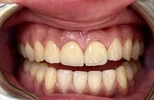

Fotoğraflar